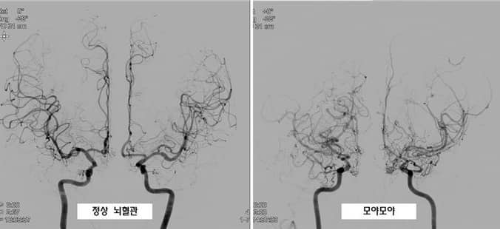

모야모야병은 뇌의 주요 혈관들이 점차 좁아지는 질병입니다. 이로 인해, 뇌에 필요한 혈액 공급이 제대로 이루어지지 않게 됩니다. 이런 현상을 보완하기 위해 뇌 내의 작은 혈관들이 활성화되어 더 많이 형성됩니다.

이 작은 혈관들의 형태가 연기처럼 흐르는 모양을 닮아 '모야모야'라는 이름이 붙여진 것입니다. 이 이름은 일본어에서 유래하였으며 연기가 구름처럼 피어오르는 모양을 뜻하는 말에서 비롯되었습니다.